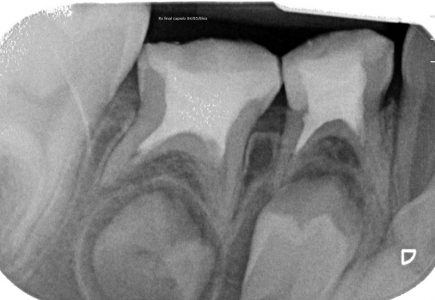

NUESTROS CASOS:

Endodoncia

Capielo